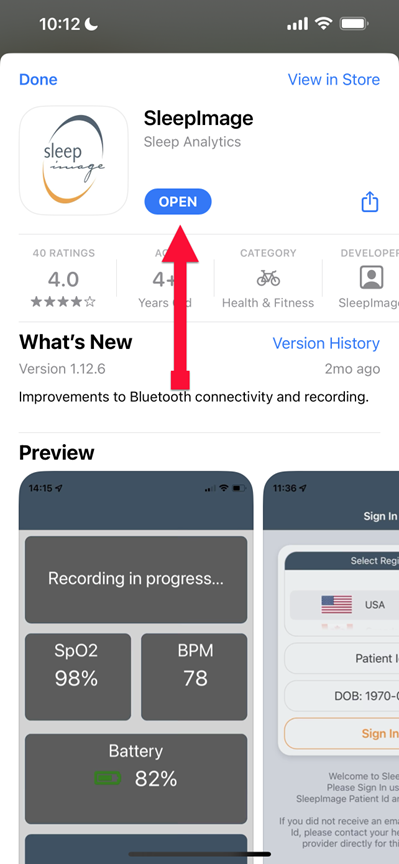

SLEEPIMAGE APP (iPhone)

SLEEPIMAGE APP (iPhone)

SLEEPIMAGE APP (iPhone)

SLEEPIMAGE APP (iPhone)

SLEEPIMAGE APP (iPhone)

SLEEPIMAGE APP (iPhone)

SLEEPIMAGE APP (iPhone)

SLEEPIMAGE APP (iPhone)

SLEEPIMAGE APP (iPhone)

SLEEPIMAGE APP (iPhone)

SLEEPIMAGE APP (iPhone)

SLEEPIMAGE APP (iPhone)

SLEEPIMAGE APP (iPhone)

SLEEPIMAGE APP (iPhone)

SLEEPIMAGE APP (iPhone)

SLEEPIMAGE APP (iPhone)

SLEEPIMAGE APP (iPhone)

SLEEPIMAGE APP (iPhone)

SLEEPIMAGE APP (iPhone)

SLEEPIMAGE APP (iPhone)

SLEEPIMAGE APP (iPhone)

SLEEPIMAGE APP (iPhone)

SLEEPIMAGE APP (iPhone)

SLEEPIMAGE APP (iPhone)

SLEEPIMAGE APP (iPhone)

SLEEPIMAGE APP (iPhone)